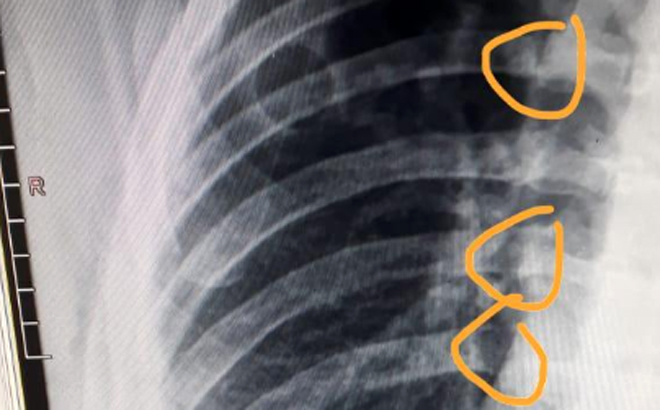

GUARUJÁ – O frentista que foi atropelado por um carro que invadiu um posto de gasolina na noite da última terça-feira (11), em Guarujá, teve quatro costelas quebradas por causa do acidente. As imagens das câmeras de monitoramento registraram esse impressionante atropelamento.

?Ele está em recuperação, vai fazer uma cirurgia, pois quebrou quatro costelas. Estamos aguardando a recuperação dele. (O meu filho) está passando por cuidados médicos no (Hospital) Santo Amaro. Quem está arcando com as consequências até agora, pagando as despesas (médicas), é o proprietário do posto. O ocorrido foi sério. Ainda bem que o caminhão dos Bombeiros estava aqui e ajudou a prestar socorro?, disse Abimael.